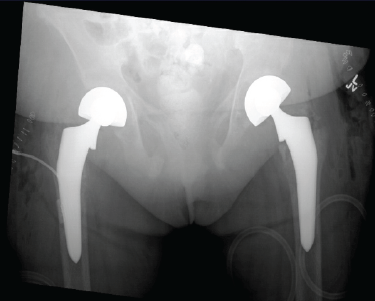

Bilateral Total Hip Arthroplasties Secondary to Renal Osteodystrophy in a Patient with a Rare Cromer Antibody: A Case Report

Anisha Tyagi , Caldon Jayson Esdaille , Ajith Kumar Kannan , Jennifer Joseph , James Lee Jr , Rahul Mittal

………………………………p.244-249